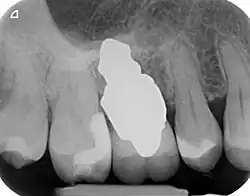

Zähne haben eine oder mehrere Wurzeln. Selbst ein einwurzeliger Zahn ist im Querschnitt oval, somit in einer Richtung oft fast doppelt so breit, wie in der anderen. Ein zylindrisches, schraubenförmiges Implantat hat im Grunde absolut keine Ähnlichkeit mit der natürlichen Zahnform, sodass systemimmanent ein invasiver chirurgischer Eingriff erforderlich ist, um das Implantat im Zahnfach im Knochen befestigen zu können. Bei einem solchen chirurgischen Eingriff muss im gesunden Knochen gebohrt und der fehlende Kontakt zwischen Implantat und Knochen muss mit Knochen oder Knochenersatzmaterial aufgefüllt werden. Im Oberkiefer Seitzahnbereich ist sogar in 98 % aller Fälle ein Sinuslift notwendig, um überhaupt ein Zahnimplantat einsetzen zu können.

Wurzelförmige Zahnimplantate werden individuell angefertigt, damit sie unmittelbar nach der Zahnextraktion perfekt in das Zahnfach eines bestimmten Patienten passen. Jedes Implantat ist daher ein Unikat und nur für einen Patienten bestimmt. Dabei muss die ursprüngliche Wurzelform geringfügig optimiert werden, sodass es sich nicht um eine einfache 1:1-Kopie eines Zahns handelt. Das Implantat füllt genau das Knochenloch nach Extraktion aus, sodass ein chirurgischer Eingriff am Knochen oder den Weichteilen nicht erforderlich ist. Die Grundform des Implantates kann vom extrahierten Zahn, aus einem Abdruck des Zahnfaches (Alveole) oder durch Segmentation aus einem CT-Scan oder CBCT-Scan hergestellt werden.[2] Wird das Implantat aus einem CBCT-Scan hergestellt, kann die Extraktion und Implantation in einem Eingriff erfolgen. Bei den anderen beiden Methoden dauert die Herstellung eines Implantats ein bis zwei Tage.

- Natürliche Form: Ein individuell gefrästes anatomisches Implantat ist der natürlichen Form eines Zahns nachempfunden, so dass es einfach in das Zahnfach passt. Wie der Originalzahn kann ein wurzelanaloges Implantat ein- oder mehrwurzelig ausgeführt werden.